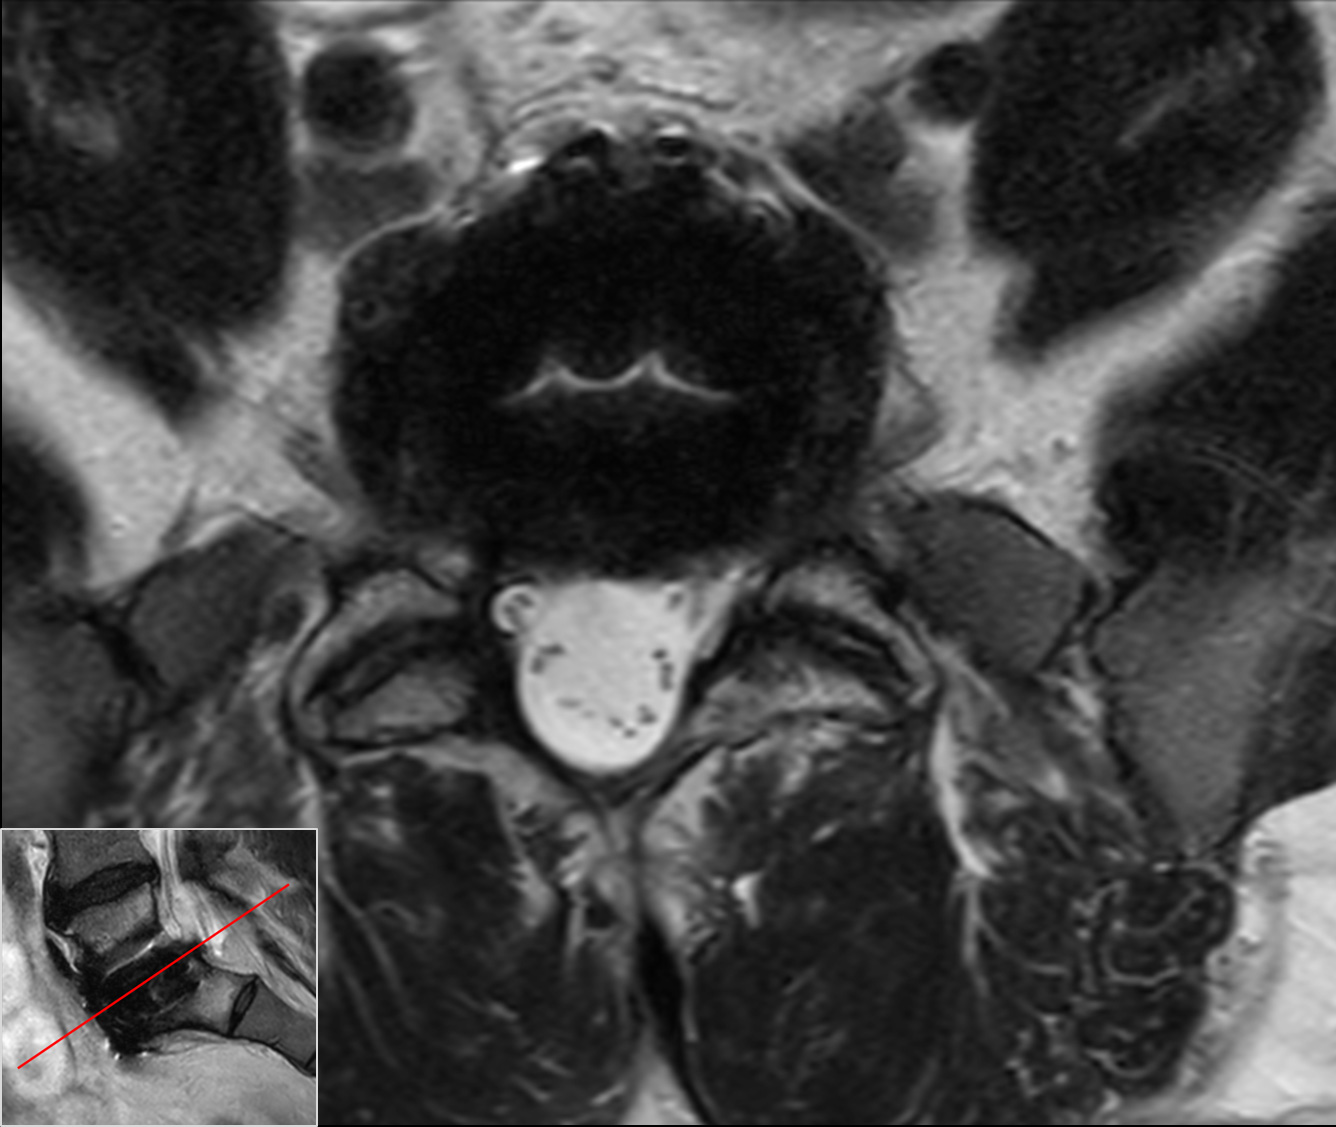

Axial T2w TSECompressed SENSE

Axial T1w TSE, post-gadoCompressed SENSE